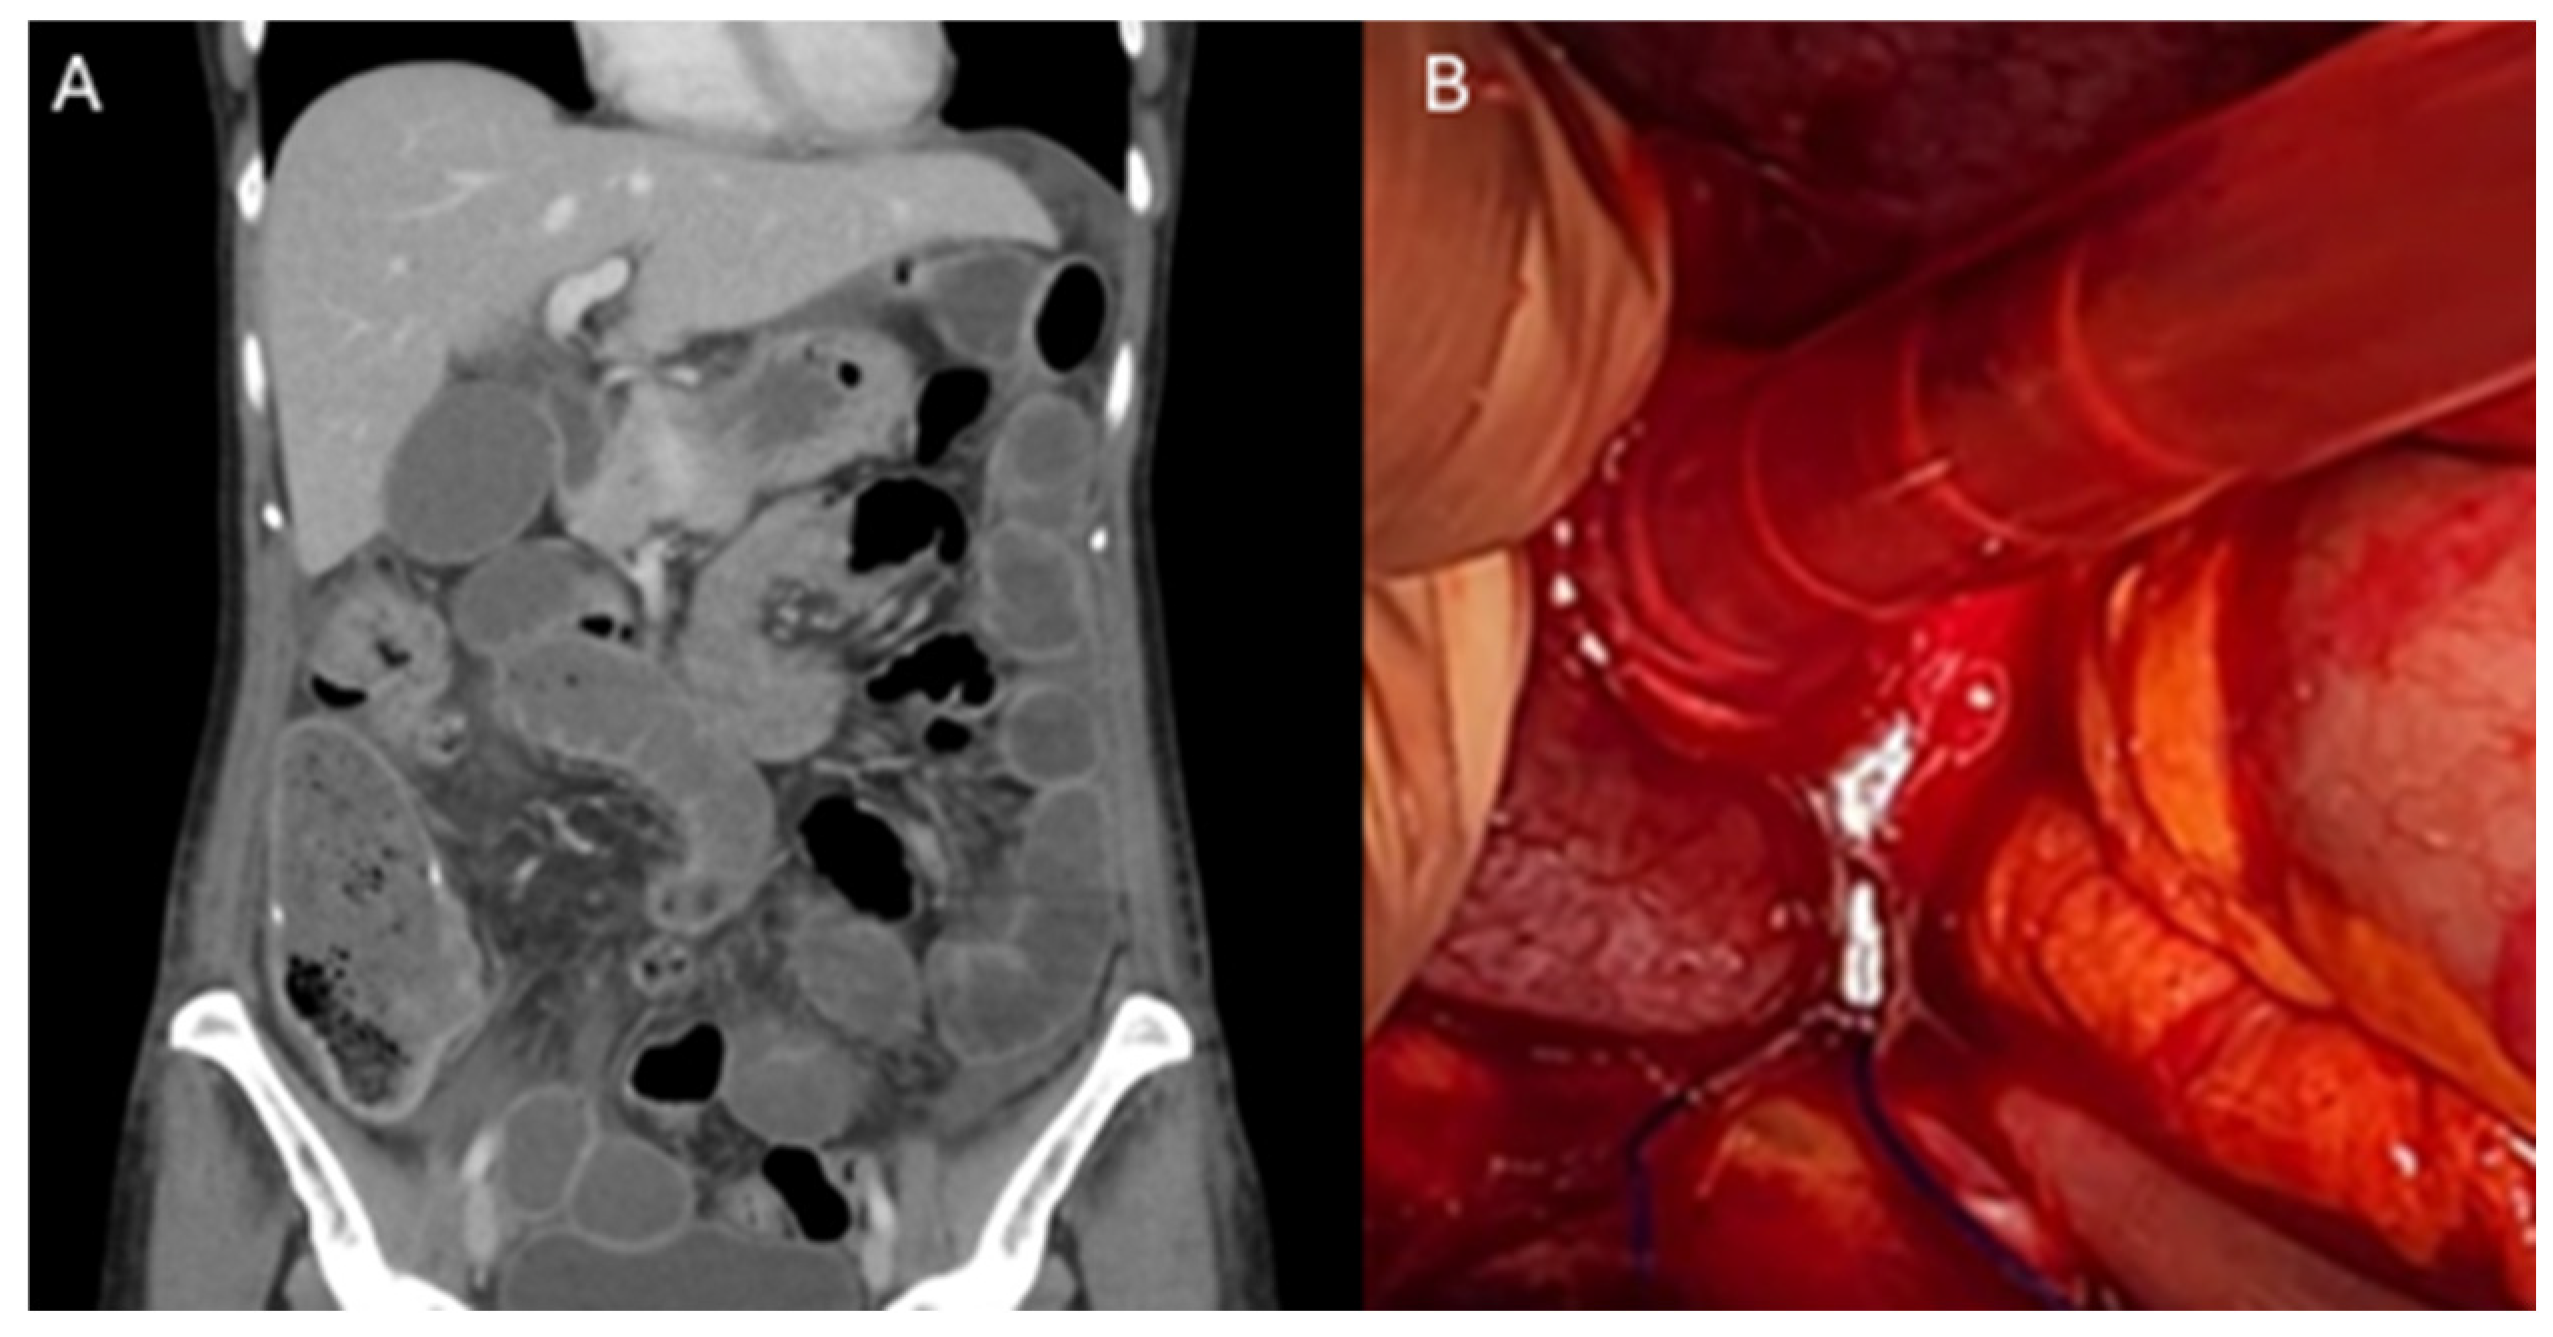

The approach to suspected small bowel obstruction secondary to a barbed suture in most cases was a diagnostic laparoscopy (88%), with only one case describing a diagnostic laparotomy as initial treatment. Intraoperatively, all the cases involved the tail of the barbed suture being adhered to the small bowel, causing small bowel obstruction (Figure 2B). Two cases reported progression of the entangled bowel to the ischaemic bowel, requiring resection. The fatty appendages of the sigmoid colon were also found to be adherent to the barbed suture tail in 25% of cases. Most cases were resolved with truncation/removal of the implicated barbed suture tail (63%). Two cases required additional small bowel resection. The average length of stay during these cases was 6 days (median 4 days), with a range from 2 to 18 days (Table 1).

Figure 2.

Small bowel obstruction secondary to entanglement in a barbed suture tail. (A) Coronal section of Computed Tomography scan of the Abdomen and Pelvis (CTAP), demonstrating distended loops of small bowel secondary to entanglement in a barbed suture tail in the pelvis. (B) Intraoperative finding of distended loops of small bowel anchored in the pelvis secondary to entanglement with a barbed suture tail.

Our systematic review identified eight cases of small bowel obstruction secondary to barbed sutures in robotic surgery. Patients undergoing robot-assisted sacrocolpopexy (RA-SCP) or procedures involving RA-SCP where barbed sutures were utilised intraoperatively had the highest rates of complications in the post operative period (50%). The additional cases reviewed were a robot-assisted radical cystectomy, robot-assisted laparoscopic Roux-en-Y gastric bypass and robotic inguinal hernia repair. RA-SCP has a very long intraoperative time that has been shown to be significantly reduced by using a barbed suture [33]. All eight of the cases reported use of the V-LocTM suture, and the majority utilised a size 3-0 V-LocTM. The V-Loc consists of unidirectional barbs with a unique dual-angle cut and an anchor loop at the other end. It is the dual-angle cut that gives a higher anchoring force compared to a single-angle cut. This unique property may also be contributing to the increased adhesive properties to bowels [18]. Intraoperatively, all cases involved the tail of the barbed suture being adhered to the small bowel, causing obstruction (Figure 2B). This is thought to be either due to most surgeons being accustomed to leaving ~1 cm of suture tail length at the end of a wound because of fear of a non-barbed suture unraveling when cut flush or not accounting for the degree of tissue shrinkage upon healing and/or developing scar tissue leading to greater exposure of the tail of the barbed suture [21].

Imaging in this subgroup of patients with Computed Tomography scans of the Abdomen and Pelvis (CTAP) typically demonstrates distension of the small bowel (Figure 2A); however, this may also appear as a volvulus. The barbed suture tail can act as a fixed point for the bowel to rotate around, creating a volvulus and potentially leading to ischaemia. CT scan findings in these cases have been found to often accurately correlate with intraoperative findings.